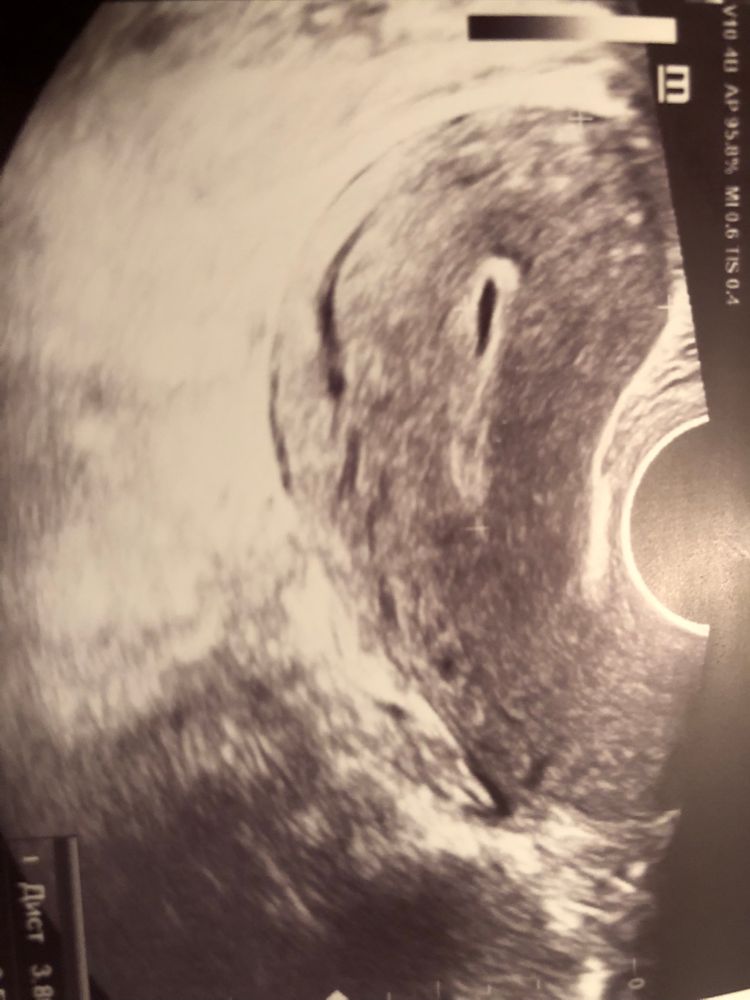

Девочки,была сегодня на узи после БХБ,месячные закончились сегодня,как бы начался новый цикл,на фото узи есть щель ,врач говорит пока неизвестно что это,у кого было так после БхБ? Это не опасно?и желтое тело тоже есть,не понимаю вообще,в заключении написано :УЗИ картина ранней пролиферативной фазы МЦ,скажите пожалуйста что за щель это может быть?

Переделать узи лучше после следующей менструации. Возможно еще будут выделения, это может быть жидкостное содержимое какое то в полости матки, не все вышло еще. На тесте почти призрак, ничего нет я бы сказала, по кр мере по фото, хгч до 10...

«Регрессирующее желтое тело» это значит что жт осталось, но оно умирает так как не пригодилось без беременности. В остальном чуть позже может посмотреть? Это не то чтобы «щель», скорее на стенке что-то, возможно остатки месячных, так как они только сегодня «кончились». Удачи 🍀